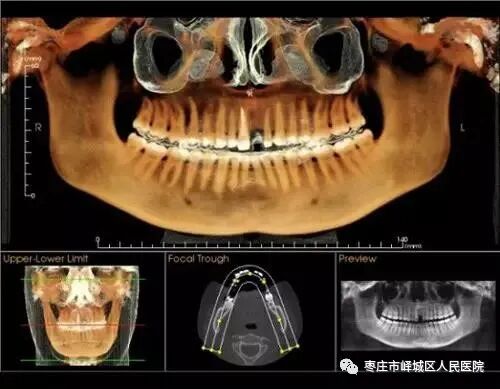

近日,峄城区人民医院引进CBCT机设备,该设备可以清晰的显示牙齿颌骨的细微结构及牙体,牙髓牙周组织牙周组水平为患者提供更加精准化的口腔疾病诊疗。

CBCT也叫口腔CT

可以从三维角度对组织情况进行反映,可以发现口腔X光片的投照角度不能发现的或者更细微的病变;它的三维重建效果能够对骨组织情况、下颌关节情况进行准确评价,协助医生进行手术前方案设计,以及术后科学评价。总的来说,与普通CT机相比,CBCT机具有分辨率高、X射线辐射小、投照时间短、费用低等优点。